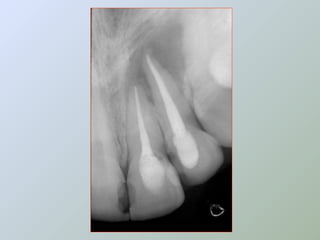

A técnica radiográfica deve ser muito bem

realizada, para a visualização adequada do

ápice radicular, e a determinação da

extensão de lesões e relações com

estruturas anatômicas adjacentes.

A amputação do ápice radicular deve ser

feita com broca montada em baixa rotação,

com abundante irrigação.

A angulação da broca em relação ao longo eixo

dental deverá ser de 90°, removendo-se desta

maneira o delta apical completamente (BERNARDINELLI

et al. 1994; BRAMANTE; CLÓVIS MARZOLA,BERBERT, 2000 e

MARZOLA, 2000 e 2002),

apesar de ainda alguns autores

serem adeptos da inclinação para vestibular

(SAILER; PAJAROLA, 2000).

Deve-se observar, também, se não há

anomalias anatômicas como: rebarbas,

intercanais, canais acessórios ou fraturas

radiculares a este nível, podendo-se

utilizar solução esterilizada de azul-de-

metileno a 2%, para identificação destas

situações (DEL RIO, 1996) e, mesmo ainda

se ocorre uma infiltração apical em

cavidade para a obturação retrógrada.

(BERNARDINELLI et al., 1994)